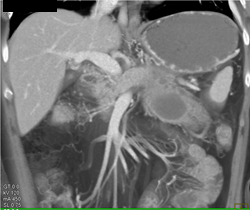

Pseudocyst S/P Distal Pancreatectomy and Splenectomy